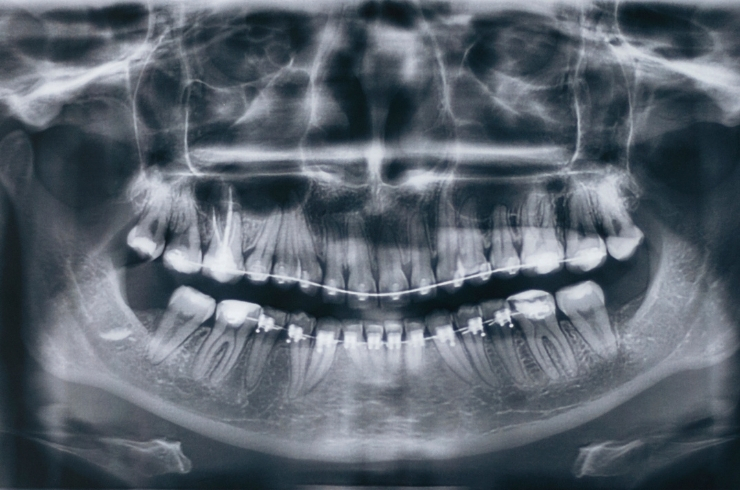

An Oral Pantomogram (OPG) is a specialized full-mouth X-ray that captures a panoramic view of your teeth, jaws, joints, and surrounding structures in a single image. It provides a clear, wide-angle picture of your oral health, helping dentists detect issues that are not visible during a routine examination. From hidden cavities and impacted teeth to jawbone health and alignment problems, the OPG delivers precise insights to guide accurate diagnosis and effective treatment planning.

What an OPG helps us assess

• Impacted teeth, especially wisdom teeth

• Jawbone health and density

• Orthodontic alignment and bite issues

• Cysts, tumors, and hidden infections

• TMJ (jaw joint) health and abnormalities

• Development of teeth in children

• Dental implant planning with accurate measurements

• Hidden cavities, fractures, and bone loss